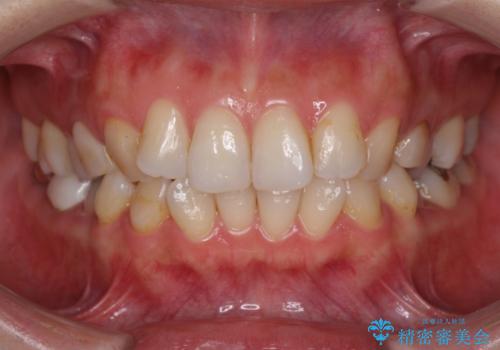

- 失活により変色した歯と不揃いな口元を気にして来院された患者様です。

口元をインビザラインにより歯列を整え、その後に失活している奥歯をオールセラミッククラウンにて補綴治療することとしました。

長時間のマウスピース装着と、患者様自身でのゴムかけに協力いただき、自然な口元に仕上げることができました。

気になっていた変色した歯もオールセラミッククラウンで本物の歯のようになり、患者様には大変満足していただきました。